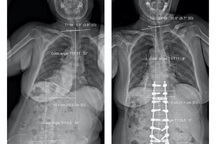

Tại Bệnh viện Trung ương Quân đội 108, qua các hình ảnh X-quang, tình trạng thực tế của bệnh nhân, các bác sĩ Khoa Chỉnh hình cột sống xác định đây là một ca bệnh đặc biệt khó, góc vẹo rất lớn T6L3 khoảng 126 độ, hơn nữa ca bệnh này càng khó khăn hơn là kèm theo gù cũng rất lớn > 100 độ.

Phim chụp X-quang trước và sau phẫu thuật nắn chỉnh gù cho bệnh nhân (Ảnh: Bệnh viện cung cấp).

Cũng bởi vì ca bệnh gù rất lớn, nên TS.BS Phan Trọng Hậu - Chủ nhiệm Khoa Chấn thương chỉnh hình cột sống cũng là bác sĩ trực tiếp mổ cho bệnh nhân A. đã quyết định cắt V xương ở 3 mức để nắn chỉnh. Để thực hiện điều này là cả một sự quyết tâm lớn, bởi vì thời gian mổ dài, kĩ thuật khó, nhiều nguy cơ tai biến, biến chứng. Sau nhiều tiếng đồng hồ, ca đại phẫu đã thành công tốt đẹp.

Sau mổ, hình thể người bệnh đã gần như bình thường, chiều cao tăng thêm vài cm, bệnh nhân A. đã cảm thấy thở dễ hơn, đi lại cũng ổn hơn, và quan trọng nhất là đã tự tin hơn rất nhiều trong cuộc sống.